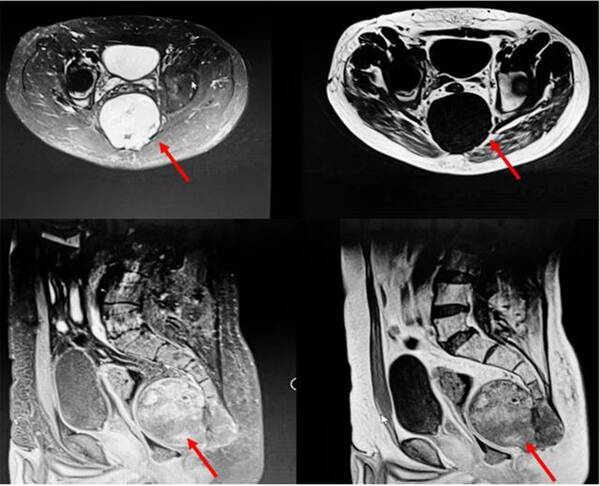

病灶巨大,達(dá)12厘米×9厘米,不僅破壞了骶骨骨質(zhì),還侵犯了臀大肌。此外,解剖位置較深,周圍結(jié)構(gòu)復(fù)雜,瘤體血運(yùn)豐富,手術(shù)暴露困難,給切除帶來了極大挑戰(zhàn)。常黎明院長、廖光軍主任團(tuán)隊(duì)多次在科內(nèi)組織病例討論,制定各種詳盡的手術(shù)方式,包括腸道切除+直腸造瘺、皮瓣移植術(shù)等多個手術(shù)備選方案。同時運(yùn)用3D打印技術(shù),根據(jù)術(shù)前患者影像學(xué)數(shù)據(jù),以1:1的比例3D打印骶骨模型,幫助術(shù)者更為清晰地了解和掌握腫瘤界限及侵犯程度,可以進(jìn)行術(shù)前的規(guī)劃和手術(shù)方案的優(yōu)化,同時為患者及家屬和術(shù)者提供觸覺與視覺上的體驗(yàn),幫助術(shù)者與患者及家屬更有效地完成術(shù)前溝通。

歷經(jīng)3小時,完整摘除“炸彈”